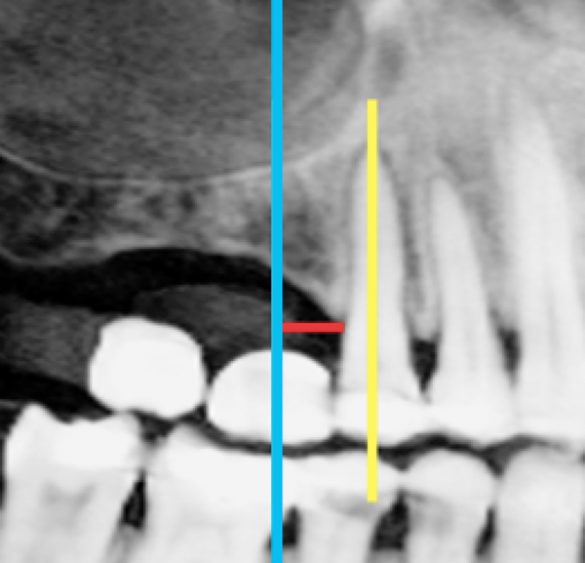

Măsurătorile din scanarea CBCT au fost înregistrate pe secțiunea transversală. O linie dreaptă perpendiculară pe o tangentă la creastă a fost extinsă până la podeaua sinusului maxilar. S-a măsurat lungimea liniei și s-a notat ca „înălțimea crestei CBCT” (fig. 1, 2). Măsurătorile periapicale ale aceleiași zone au fost înregistrate prin extinderea unei linii drepte paralele cu axul lung al dintelui natural sau implantului adiacent, de la creasta alveolară până la podeaua sinusului maxilar. Lungimea liniei a fost măsurată și înregistrată ca „înălțimea crestei PA” (fig. 3).

De asemenea, orientarea setărilor planului de referință au un impact asupra măsurătorilor liniare.18 Acest lucru poate fi vizualizat în fig. 10, care prezintă un exemplu pentru diferite măsurători liniare obținute cu o setare a planului de referință cu +/- 12°. În prezentul studiu, s-a verificat setarea planului de referință, pentru a avea linia secțiunii transversale paralelă cu dintele adiacent, așa cum se vede în fig. 1-3.